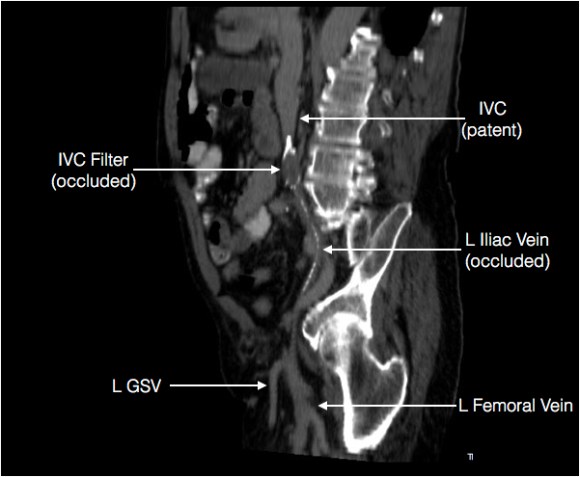

It showed an Optease retrievable vena cava filter that was occluded and the iliac systems bilaterally (right above and left below) were chronically occluded with patent vena cava above and femoral confluences bilaterally below.

Annotated L iliocaval Centerline Preop CT.jpg

Left iliocaval system showing chronic occlusion on centerline projection